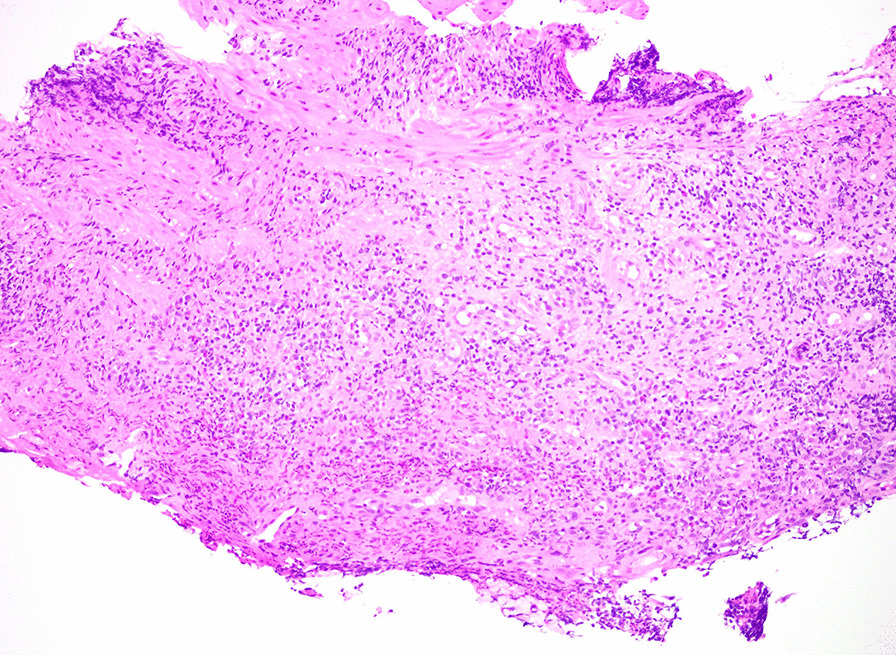

We performed esophagogastroduodenoscopy that revealed Los Angeles Grade C esophagitis (involving ≥ 1 mucosal breaks continuous between tops of ≥ 2 mucosal folds, < 75% circumferential) (Fig. 1). Histopathological analysis of esophageal biopsies demonstrated granulation tissue with acute and chronic inflammation (Fig. 2). Periodic acid-Schiff-diastase staining was negative and immunohistochemical stains for herpes simplex virus and cytomegalovirus were negative. There was no evidence of eosinophilic esophagitis. He was diagnosed with esophagitis secondary to vaping. We treated him with intravenous 40 mg twice daily PPI and analgesics until he was able to tolerate oral intake. He was counseled extensively on vaping cessation. The patient reported complete resolution of symptoms after 2 months of PPI therapy and vaping cessation.